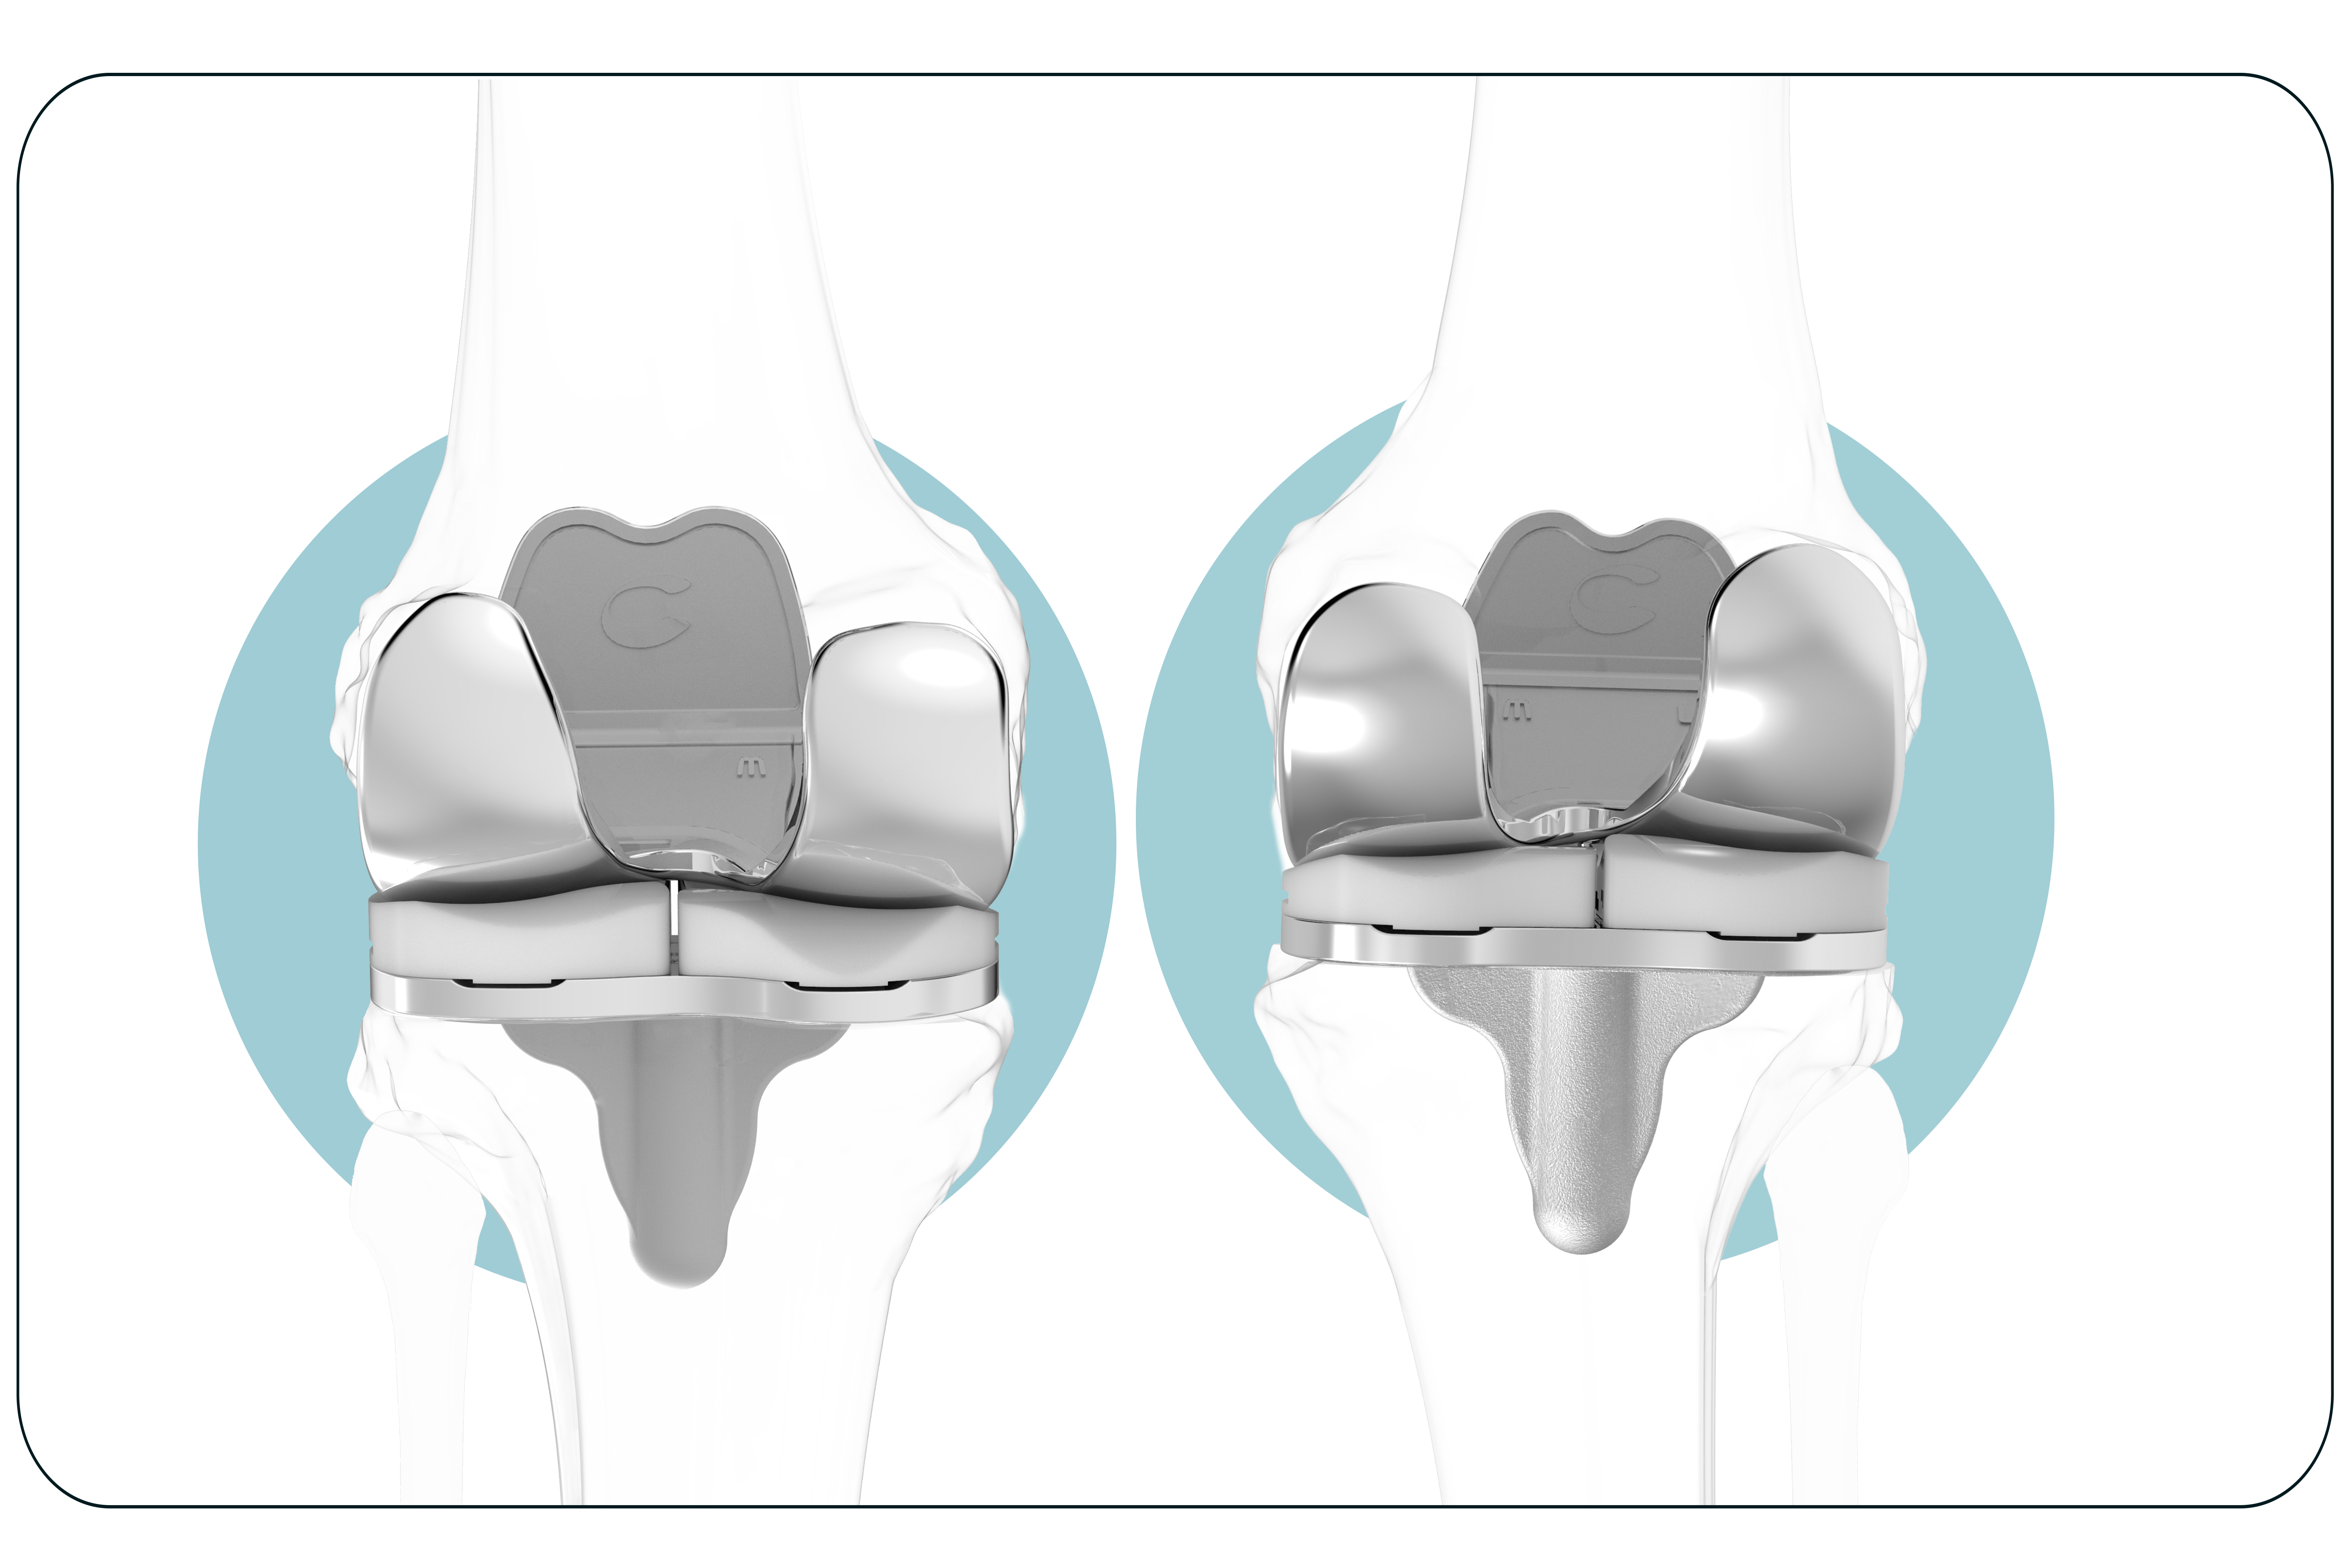

Un paciente. Un implante

Ajuste individualizado

que prácticamente elimina las dolencias ocasionadas en pacientes con otro tipo de prótesis de rodilla.

Consigue una sensación más natural

Prótesis de rodilla 3D está diseñada para seguir la forma y el contorno de la rodilla de cada paciente, proporcionando un mayor potencial para su rodilla con una sensación más natural.

Evita la inestabilidad

Mantiene las líneas naturales de la articulación del paciente para evitar la inestabilidad, causa común de la insatisfacción del paciente.